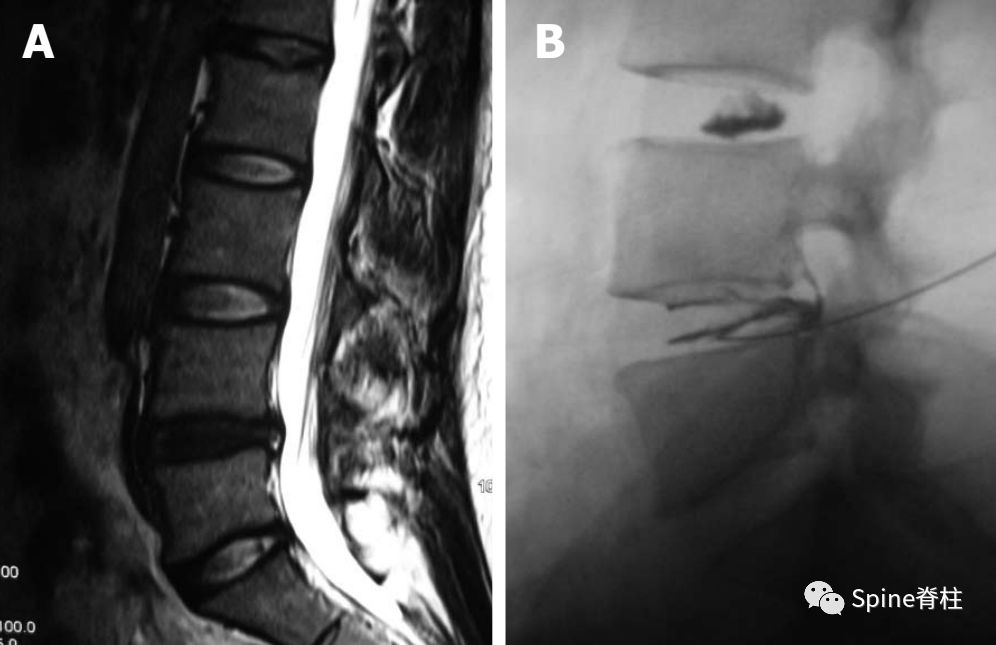

这个腰椎MRI符合上述病人的影像学结果,但很多基层医院医生会给予“腰椎间盘突出”的诊断,其实,最可能的诊断应该为“椎间盘源性腰痛”。

椎间盘源性腰痛是指椎间盘病变后刺激椎间盘内疼痛感受器引起的慢性腰痛,不伴根性症状,但可伴有腹股沟区及大腿前侧牵涉痛。通过腰椎间盘造影术,彭宝淦教授等将椎间盘源性腰痛分为两种类型,即由纤维环破裂引起的腰痛 (Internal annular disruption, IAD)和由终板破裂引起的腰痛,即终板源性腰痛 (Internal endplate disruption, IED),这种分型方法有充分的临床和理论根据。临床上这两种类型的腰痛都要通过腰椎间盘造影术确诊,操作过程、放射状撕裂方式和疼痛反应判定完全一致。疼痛的椎间盘在造影剂注射过程中,造影剂要么通过放射状纤维环撕裂流向椎间盘外方,要么通过放射状终板撕裂流向椎体,两者都诱发患者平时的腰痛反应。

椎间盘造影机制。A:椎间盘内注射的造影剂流向纤维环;B:椎间盘内注射的造影剂流向终板